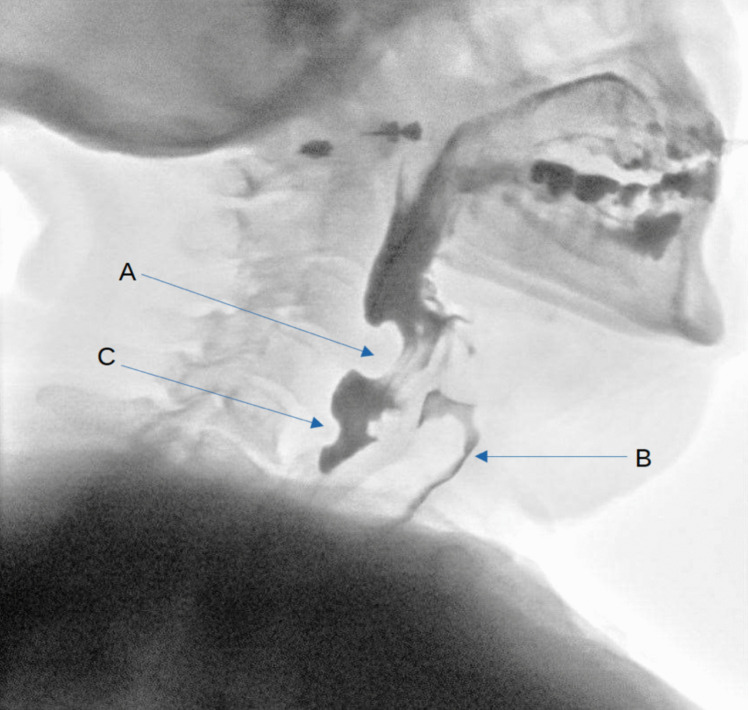

Purpose: We present a case of dysphagia caused by an aberrant internal carotid artery (ICA). By reporting this rare occurrence, we hope to highlight the anomaly as a differential in cases of persistent, progressive dysphagia.

Results: Even though the symptomatic mass effect of the ICA warranted the option of surgical intervention, due to a patient-centered approach with an emphasis on personal preference, the patient was instead referred for specialized ergotherapy.